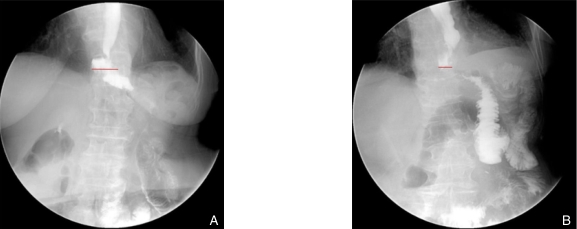

图2 患者术后上消化道造影典型图像(红色为吻合口长径测量线) A:L+H关闭组;B:传统关闭组Fig.2 Typical postoperative upper gastrointestinal contrast images of patients (the red line indicates the measurement of the anastomotic longitudinal diameter) A: L+H closure group; B: Conventional closure group